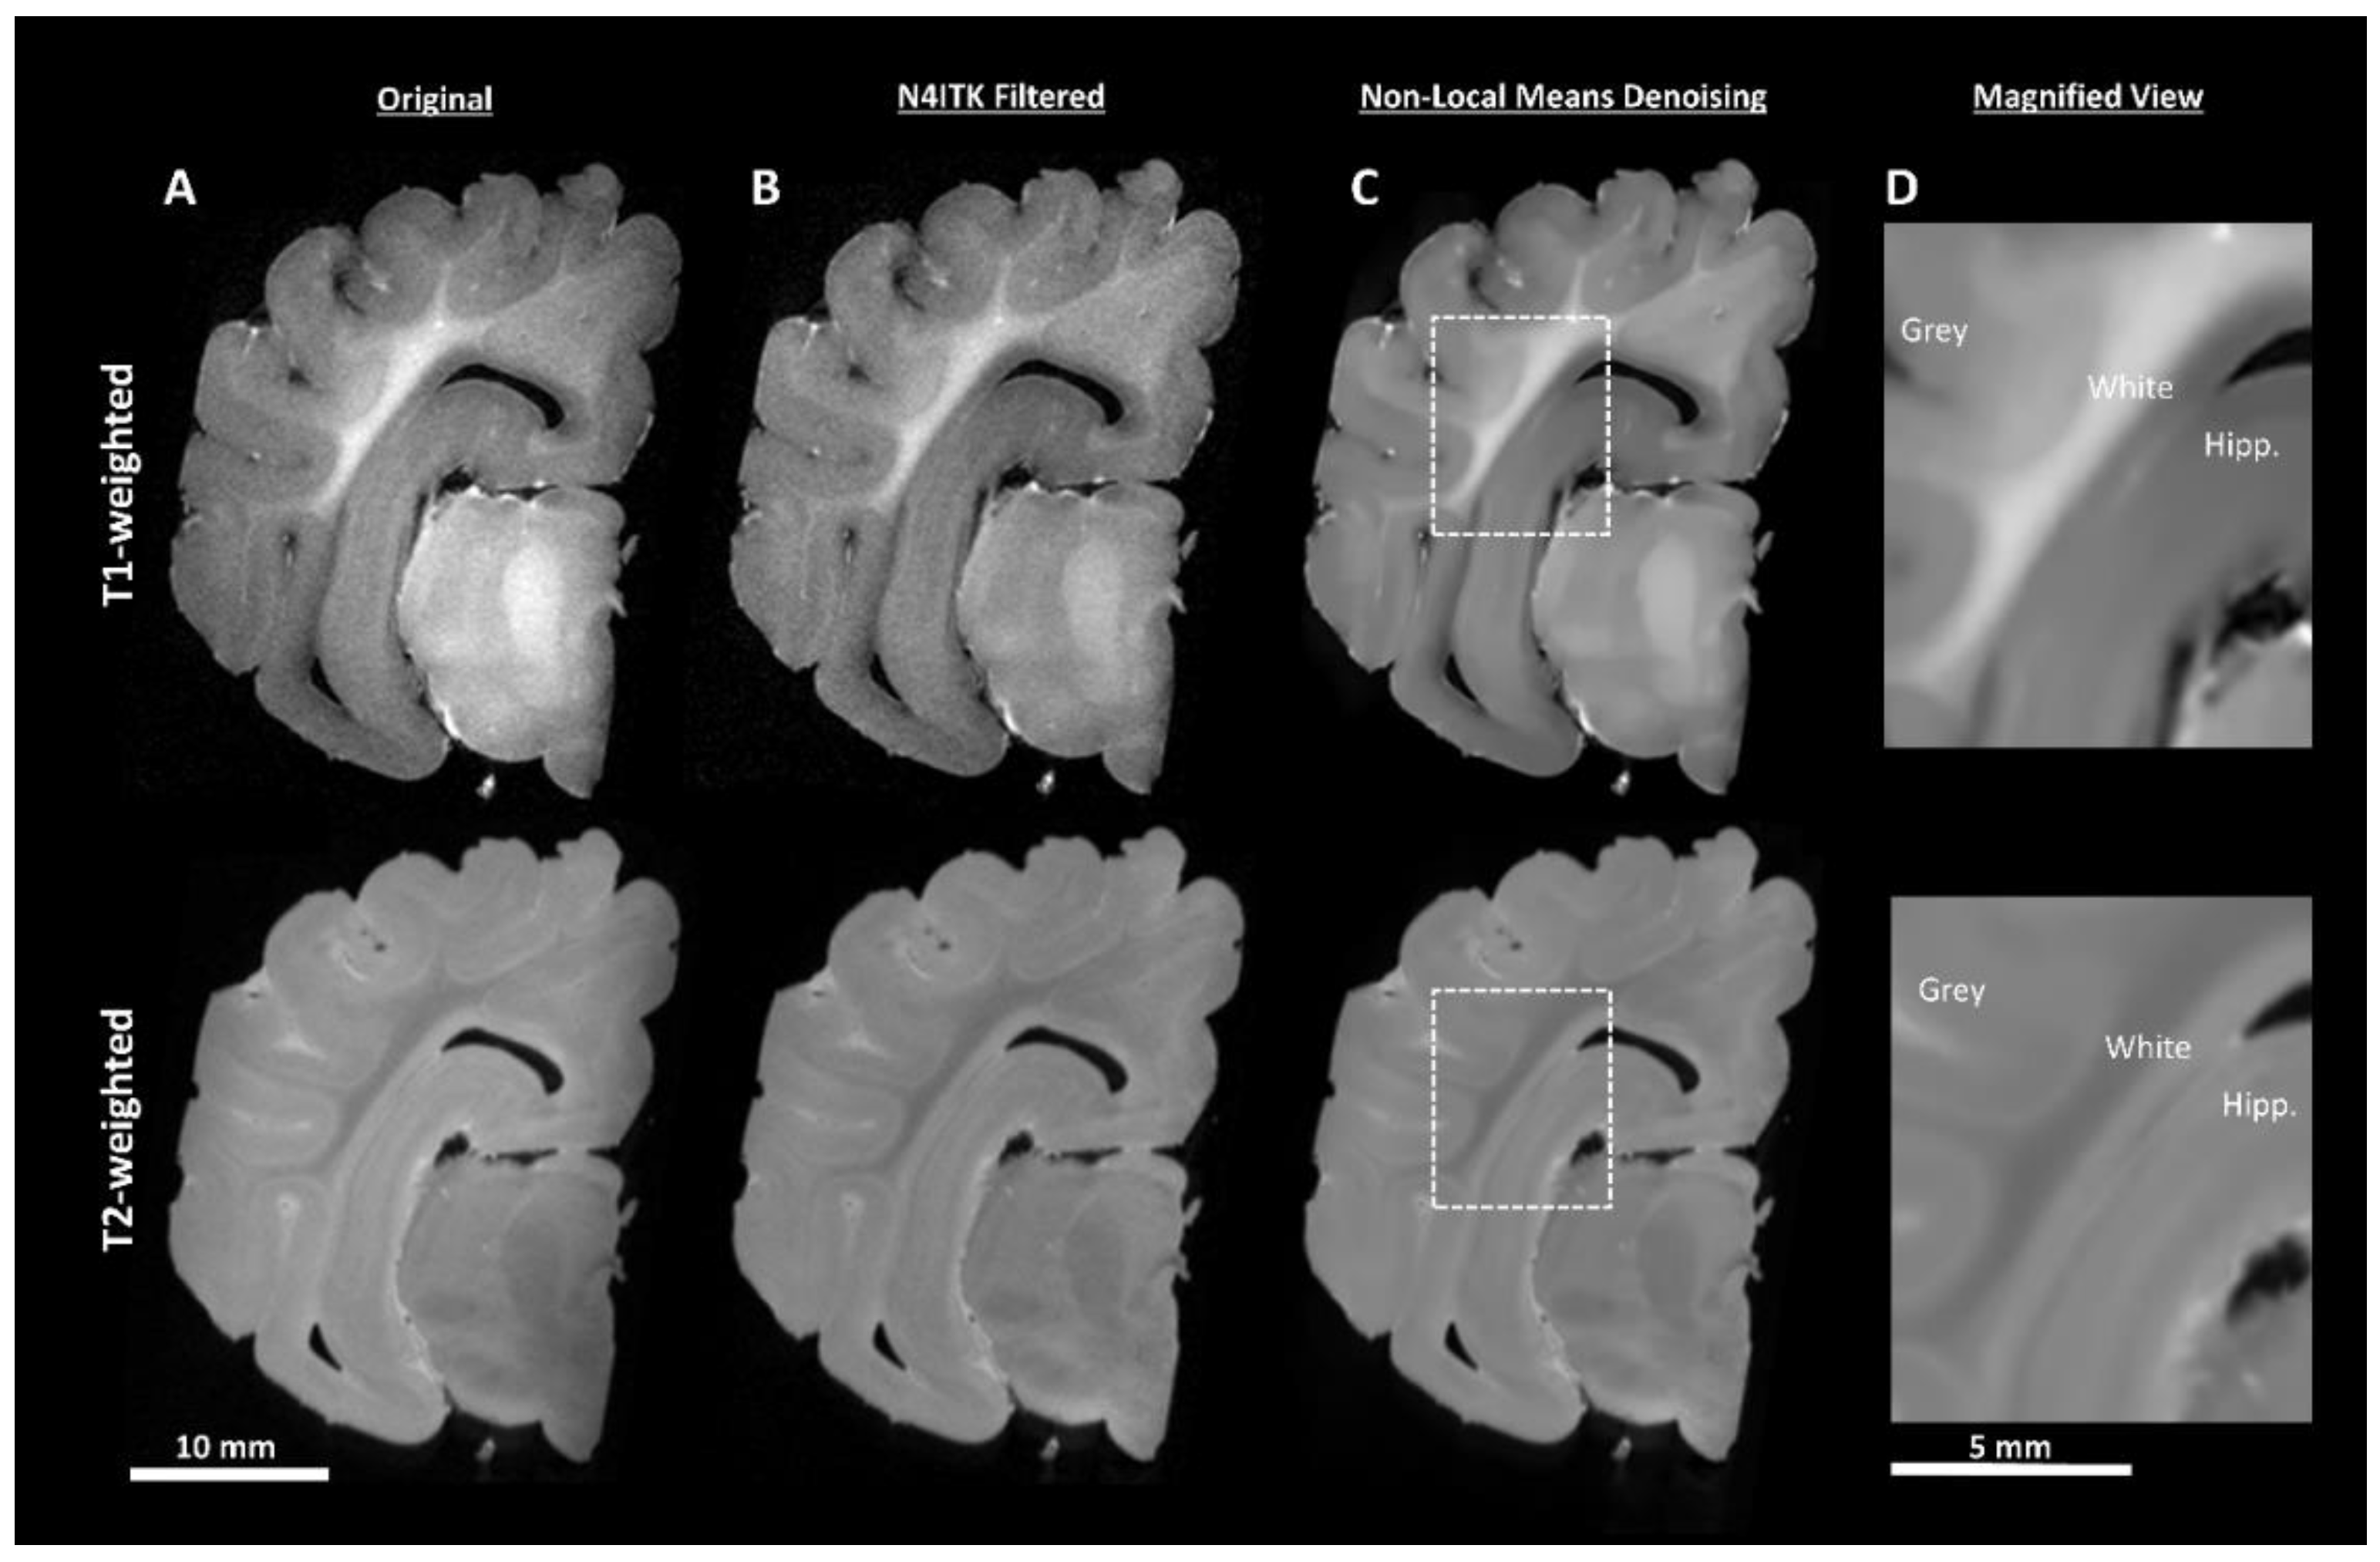

2.4.1. Pre-Processing

DICOM (https://www.dicomstandard.org/) files were batch converted to the NIfTI format (https://nifti.nimh.nih.gov/) using MRIcroGL (https://www.mccauslandcenter.sc.edu/mricrogl/). MRI images often exhibit a low-frequency intensity variation known as the bias field (Figure 3A). The N4ITK [19] module in 3D Slicer (Version 4.80, https://www.slicer.org/) [20] was used to perform bias field correction (Figure 3B). Noise attenuation was performed using a MATLAB implementation [21] of the non-local means algorithm (Figure 3C), which uses adaptive 3D averaging based upon voxel similarity and not only geometric proximity [22]. At this stage it was apparent that the T1-weighted sequence demonstrated better white/grey matter tissue contrast, showed more consistent image appearance, and was better able to delineate the hippocampus from surrounding tissue than the T2-weighted sequence (Figure 3D). Therefore, only T1-weighted images underwent further processing for segmentation. Finally, the images were manually re-orientated to a common alignment plane using FreeSurfer (version 6.0) [23], to ensure that anatomical orientation labels were correct.

Figure 3.

Image pre-processing demonstrated by T1- and T2-weighted coronal sections (A). N4ITK bias field correction (B) removes bright and dark patches in the image resulting in more uniform tissue-type intensity. The use of non-local means denoising (C) attenuates the high-frequency noise in the image, creating more uniform tissue boundaries. A magnified view of the boxed regions is shown in (D) encapsulating part of the cortex (White and Grey) and hippocampus (Hipp.) All images within each have normalized histograms to allow for quality comparisons.